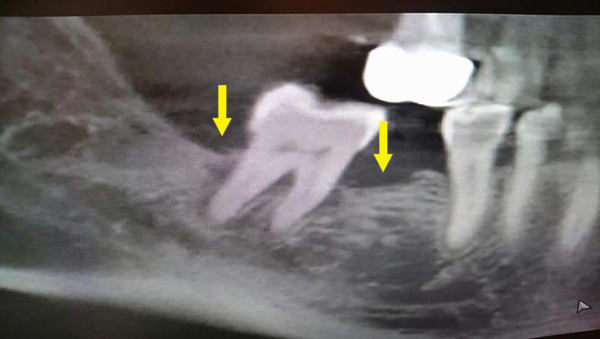

矯正後因牙周病造成骨缺損,電腦斷層上可見明顯骨缺損(紅色箭頭處),經牙周組織再生手術,合併人工骨粉、再生膜及生長因子進行組織重建,術後半年可見明顯之骨再生(黃色箭頭處)。

術前:![]() |

術後:![]() |